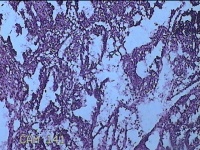

子宫腔内组织

性别

女

年龄

39岁

临床诊断

早期人工流产

一般病史

停经36天。

标本名称

大体所见

灰白暗红色不规则碎组织3x2.5x1.3cm一堆,未发现明显的绒毛样组织。

不具诊断价值。

在切片质量方面还需要加把劲。